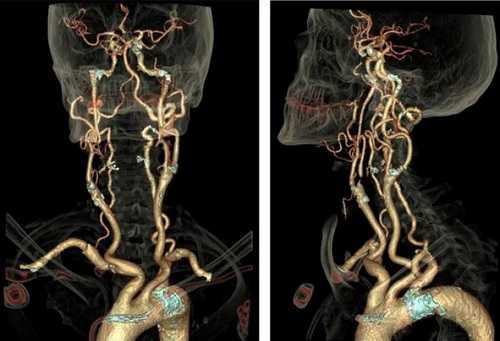

— Это современный и один из наиболее информативных методов диагностики патологии сосудов, основанный на применении рентгеновского излучения. От обычного рентгена его отличает гораздо большая информативность. Врач с помощью специальной программы может сформировать трёхмерную модель сосудов исследуемой области.

КТ-ангиография всегда выполняется с контрастом, то есть с внутривенным введением контрастного препарата. Так кровеносные сосуды становятся более заметными на снимках по сравнению с окружающими тканями. Это даёт возможность с высокой точностью оценить их просвет, расположение, синтопию (взаимоотношение с окружающими анатомическими структурами) и прочие параметры. Эти параметры определяют доступность сосудов для хирурга, например, при планировании вмешательств. Всю эту информацию мы стараемся отразить в протоколе максимально подробно (особенно если направляющий врач в направлении ставит перед нами конкретные вопросы).

— КТ-ангиография широко используется с целью оценки сосудов головы, шеи, крупных сосудов брюшной полости и забрюшинного пространства, сосудов подвздошных областей, нижних конечностей, коронарных артерий, а также лёгочных артерий и вен.

КТ-ангиография кровеносной сети головного мозга

Мультиспиральная КТ ангиография, трехмерная визуализация

КТ ангиография позволяет создать трехмерную реконструкцию сосудистой системы на определенном участке. В отличие от классической рентгенографии в результате исследования получают серию послойных изображений с заданным шагом. Толщину сканирующего среза настраивают индивидуально (от 1 мм). На основании поперечных, боковых и прямых фото создают 3D-модель рассматриваемой области.